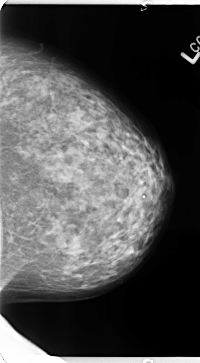

B_3133_1.LEFT_MLO

LEFT_MLO LINES 4664 PIXELS_PER_LINE 2608 BITS_PER_PIXEL 12 RESOLUTION 50 NON_OVERLAY